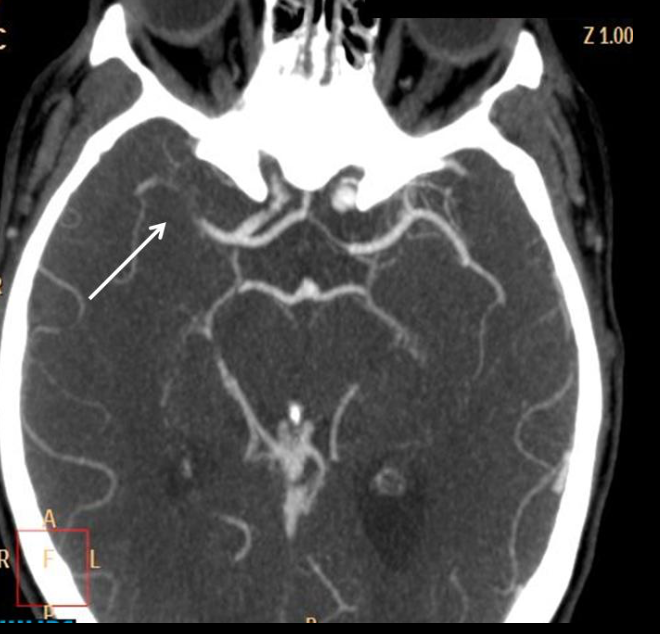

A

EVC hemorragico

AngioTC